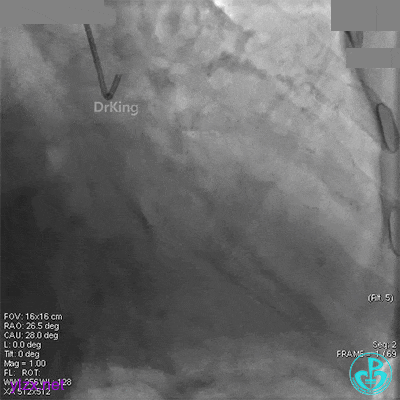

冠脉造影

回旋支近段狭窄约80%,中段以远完全闭塞。

LAD近中段弥漫性狭窄约50%,第一对角支开口及近段狭窄约80%。RCA近段至中段狭窄约80%。